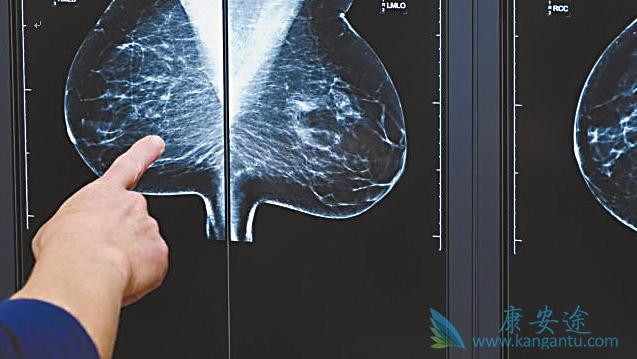

乳腺癌是女性高发的一种癌症,也是女性肿瘤的头号杀手,许多女性由于平时生活比较繁忙忽略了自身的癌症检测,导致了很多乳腺癌发现时就已经是晚期,晚期乳腺癌的治疗效果很不理想,存活率也很低。但如果乳腺癌在早期被发现,那么将很好治愈,对此海外医疗研究专家提醒你一定要注意一下几点早期乳腺癌症状。